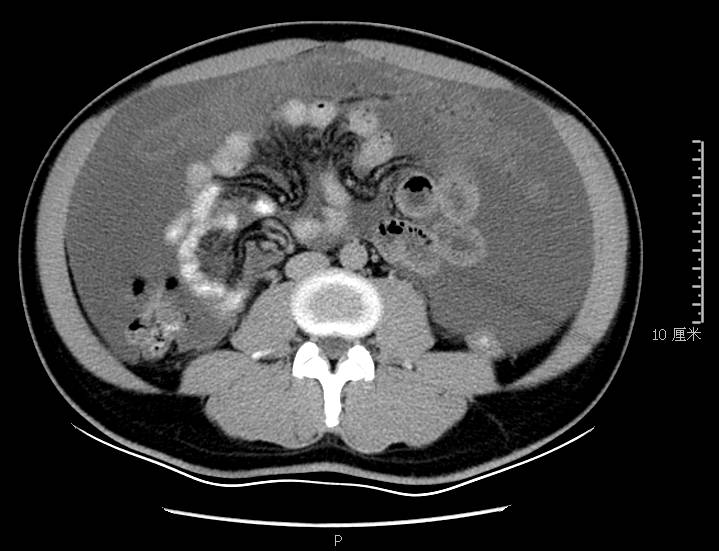

全腹CT:(1)结合病史考虑腹膜炎(见图2A),大量腹水;(2)右骼窝区管状样结构,考虑阑尾扩张(见图2B);(3)肝脏多发小囊肿(见图2C);(4)肝内胆管轻度扩张,建议隔期复查。

图2a大网膜成饼状(CT腹腔横断图象上出现肠曲被前面及两侧的肿瘤组织限制在中央

图2b扩张成管状阑尾

本例确诊后对B超及CT再次回顾发现:腹腔、盆腔可见不均质中强回声包块,部分呈囊实状,腹膜增厚,大网膜成饼状(如图2A)和肝周可见不均质中强回声弧形压迹、脾周可见不均质中强回声包饶,肝脏成扇贝样改变(如图2C),但在诊断报告中未提及。有学者发现mantle和scalloping(如图2A,2C)在PMP中具有代表性,且mantle较scalloping更为常见,若mantel征同时伴有大小不一的囊性改变,则更具诊断价值。

图2c肝脏成扇贝样改变(肝脏由于受肿瘤实质性或囊性组织压迫而其实质却未受侵犯,于是在一处或多处呈下凹状或扇形皱褶状(scalloping)